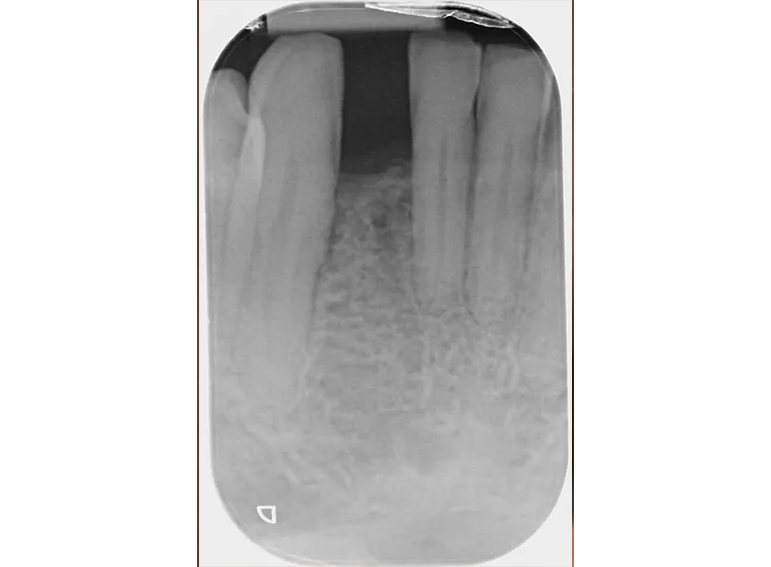

Missing lower incisor replaced with an adhesive bridge.